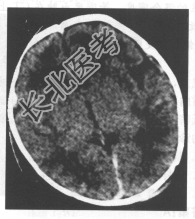

- 单项选择题患儿,女, 15天。吸吮反射减弱,CT检查如下图。最可能的诊断为

A、脑水肿

B、新生儿缺氧缺血性脑病

C、脑出血

D、先天性无脑回

E、先天性巨脑回